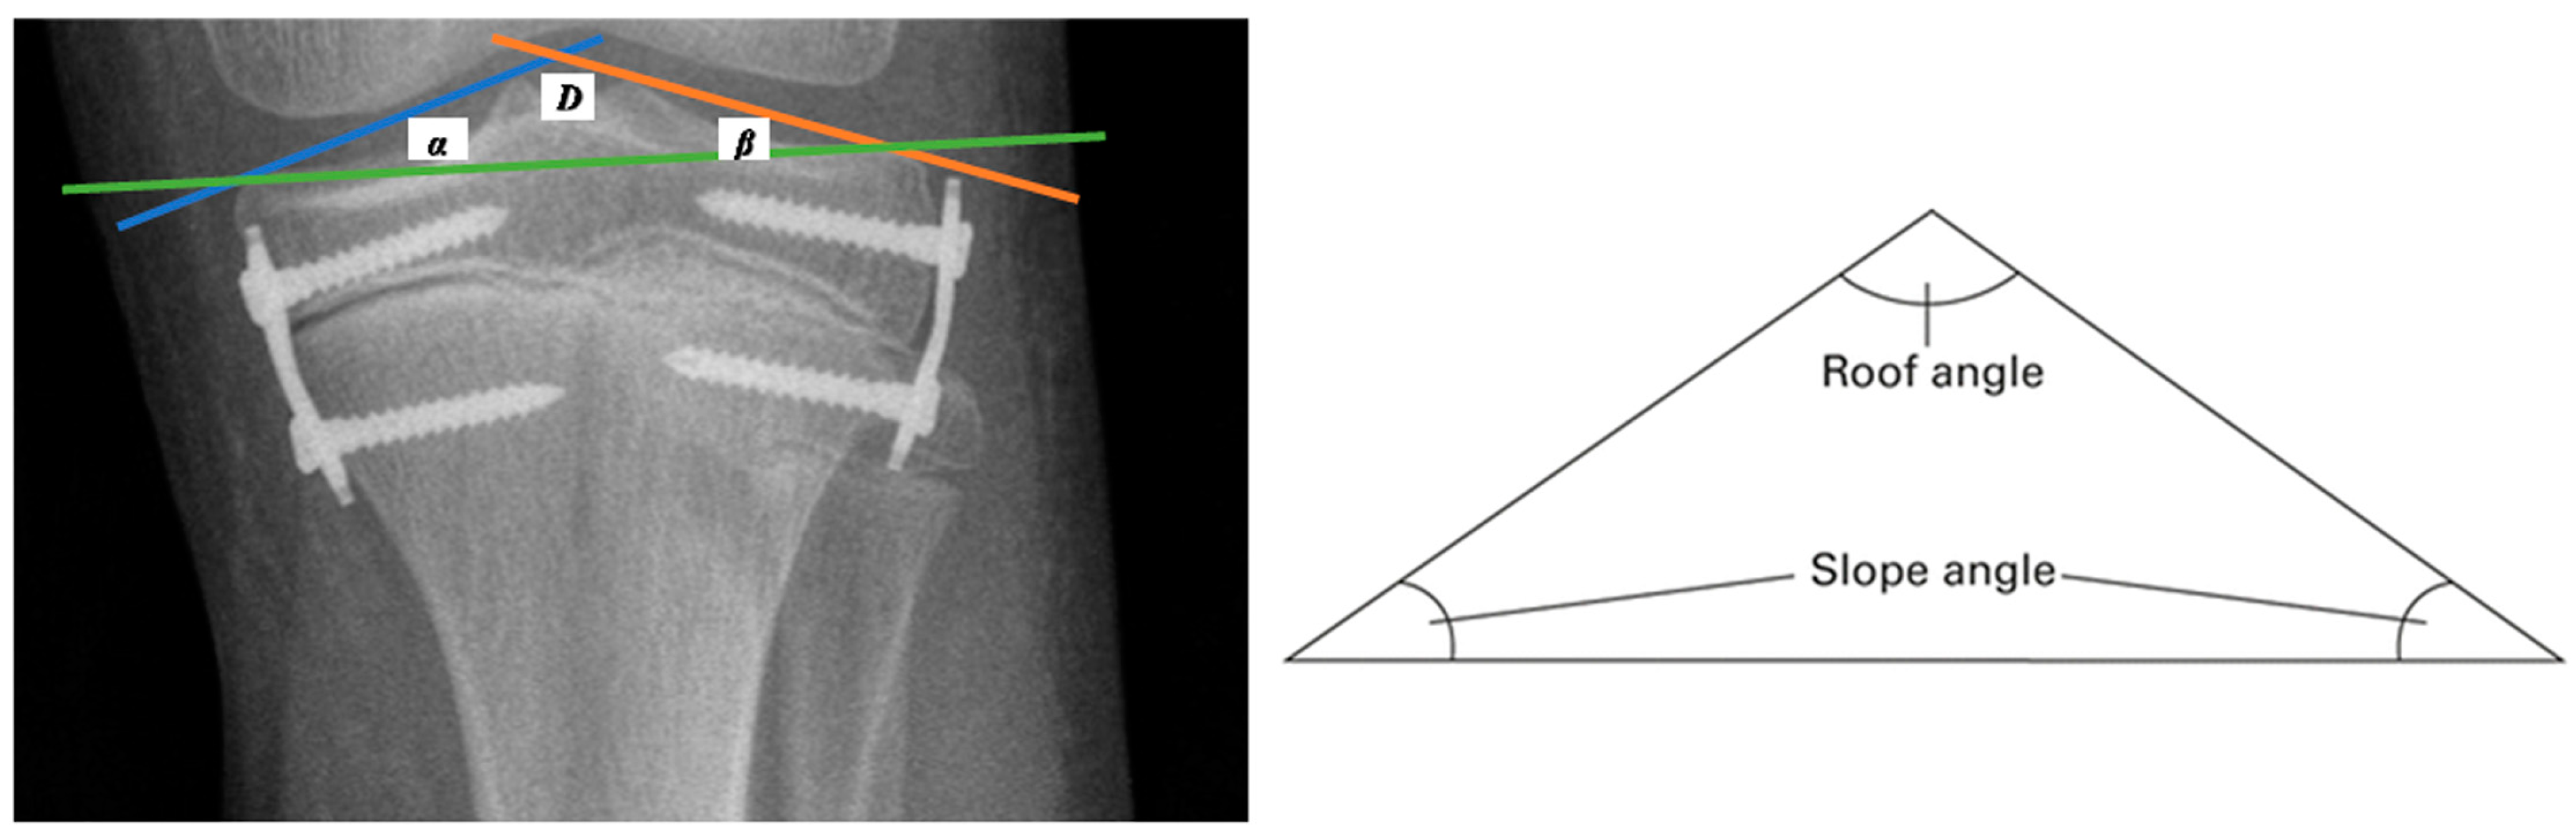

Radiographs taken before the planned epiphysiodesis procedure and at intervals of +/− 6 months until the end of the treatment were assessed. A full-length standing AP radiograph of the lower limbs (body X-ray) was used to assess angular and linear parameters. A single radiographic exposure of both lower limbs was performed, with the radiation beam centered on the knees from a distance of approximately 180 cm and the patient standing upright with both patellas pointing directly forward. To illustrate changes in the tibial plate surface expressed in degrees, measurements of the angles of the triangle proposed by R. Sinha from the connection of the tibial articular line (the line connecting the external highest points of the tibial condyles—green line in Figure 2), the medial line of the tibial plate inclination (the line between the highest point in the projection of the medial intercondylar tubercle and the point defining the outermost upper end of the medial condyle—blue line in Figure 2) (angle α), and the lateral line of the tibial plate inclination (the line between the highest point in the projection of the lateral intercondylar tubercle and the point defining the outer highest upper end of the lateral condyle—orange line in Figure 2) (angle β) were performed [7].

Figure 2.

A graphic image of the tibial articular line (green line), the medial line of the tibial plate inclination (blue line), and the lateral tibial plate slope (orange line), as well as a graphical representation of the roof angle.

The “tibial roof” angle (D) is included between the medial and lateral lines of the tibial plate inclination, defined as the result of the difference in the acute angles of the triangle formed by the lines (the medial tibial plate inclination line, the lateral line of the tibial plate inclination, and the tibial articular line (180 minus α, minus β)) [7].